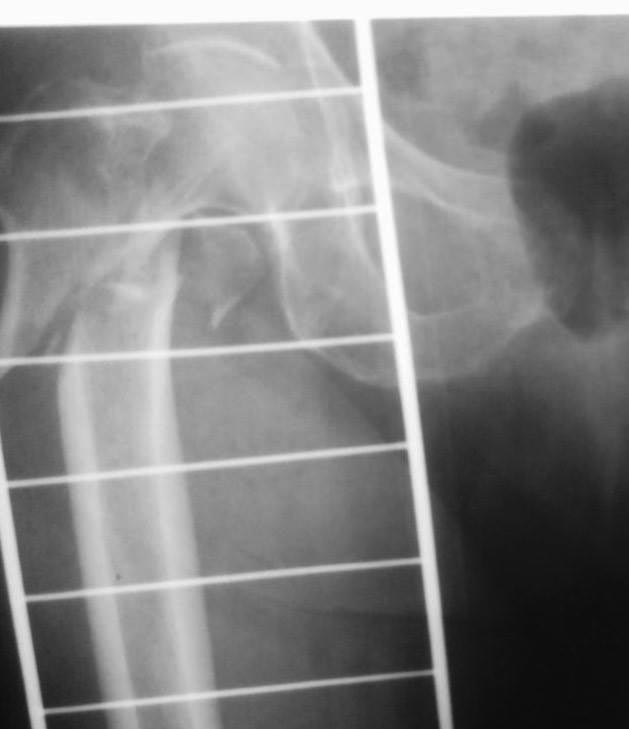

Как-то так

Это длинная псевдограмма, как понимаете, Ее сложно сзади завести, с ЭОПа только эта картинка, я за соседним столиком оперировал, парни пытались погнуть - обломился, в итоге поставили короткую, репозиция примерно такая же, снимки могу завтра -послезавтра выложить. У нас уже были проблемы с этим стержнем в плане переднего Кортекса, да и другие тоже, у них на проксимальный винте не "борозды" , а "царапины" - либо блокировать наглухо либо ротационной стабильности нет, да и прямая как шпага((((

заднего захода тут точно нет,а чуть кпереди - здесь бы ничего не решило (делали и так). Это уже не первый раз такое с этими гвоздями. Просто уже накипело. Чуть поуже или покривее бедро - упираются в передний кортекс. У многих что-то вроде tip pain. Было 2 периимплантных перелома, на мой взгляд связанных именно с этим. Сломался по дырке, мне кажется и в тисках не получится, сплав какой-то непластичный совсем.